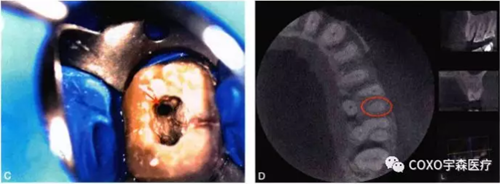

(三)顯微放大系統(tǒng)檢查

細(xì)小鈣化根管的根管口,即使是在口腔手術(shù)顯微鏡下,也不容易被發(fā)現(xiàn)。在鈣化根管的早期,鈣化牙本質(zhì)的顏色可能與周圍正常牙本質(zhì)不同,因此,多數(shù)情況下,利用口腔手術(shù)顯微鏡能夠發(fā)現(xiàn)根管所在位置。有的鈣化根管牙本質(zhì)與周圍牙本質(zhì)顏色相似,難以區(qū)分,此時(shí)借助手術(shù)顯微鏡的高倍放大作用,結(jié)合根管解剖知識(shí),仔細(xì)觀察顏色的細(xì)微差異,有助于提高探查根管口的成功率。完全鈣化的根管,表現(xiàn)為均質(zhì)的硬組織結(jié)構(gòu),有時(shí)與正常牙本質(zhì)結(jié)構(gòu)難以區(qū)別,當(dāng)采用各種方法均無法疏通時(shí),為了避免產(chǎn)生新的并發(fā)癥,不宜強(qiáng)行疏通,可定期追蹤觀察(圖4-2)